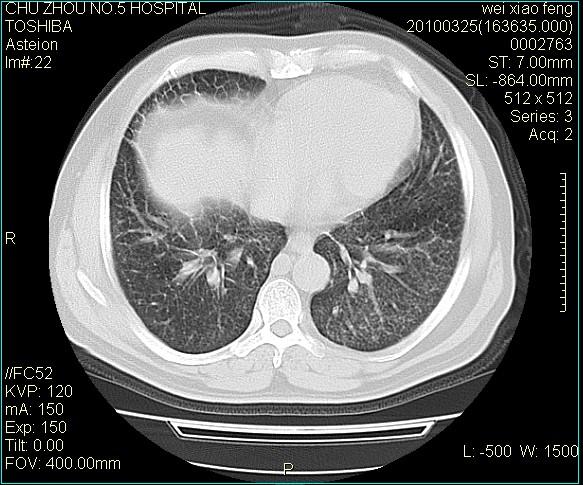

男,60岁,反复咳、痰、喘3月,加重3天。

双肺间质性改变。

考虑双肺血型潘散肺结核/

间质性肺炎伴间质纤维化!不排除伴有职业病!

急性血型潘散肺结核。

双肺间质纤维化,双肺血型潘散肺结核。

考虑间质性肺炎伴间质纤维化。

间质病变,间质炎症,间质纤维化趋势

右肺中叶结节影为原发灶,考虑右肺中叶周围型肺癌并淋巴道转移

间质性肺炎